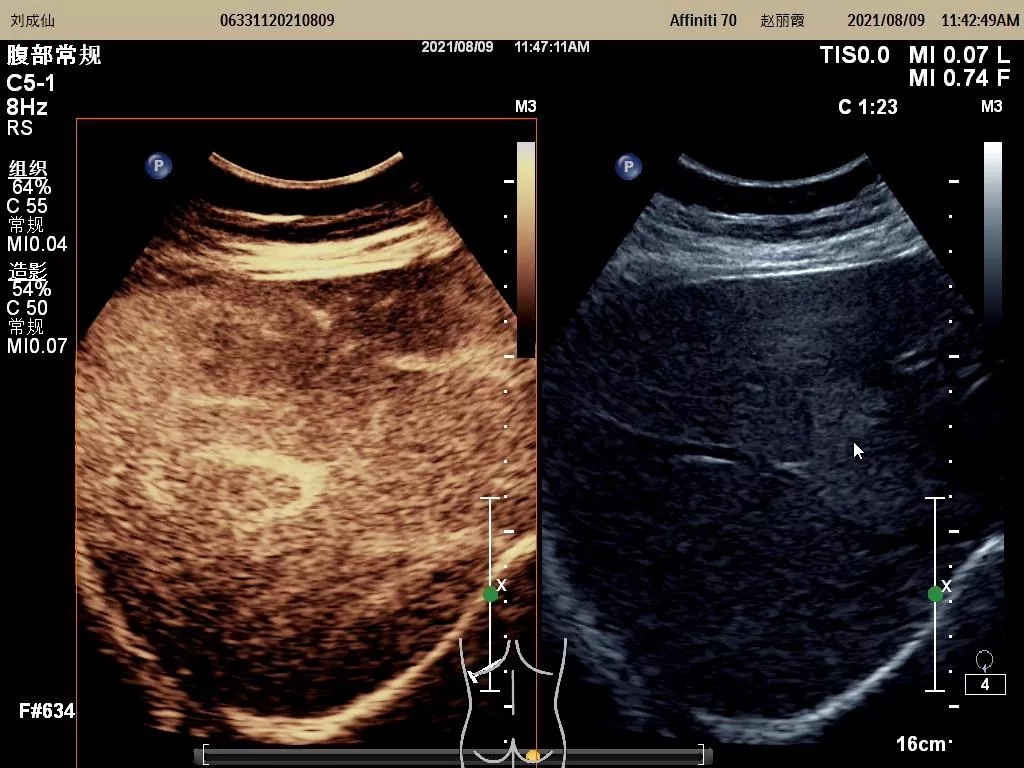

自我院功能检查科成功开展市内首例超声造影检查技术后,近期又开展了多例脏器(包括肝脏、甲状腺、乳腺、淋巴结等)超声造影术。该技术的全面成熟开展,标志着我院超声造影检查技术再上新台阶,必将进一步推动陇南地区超声医学专业的发展。

图为开展的肝脏超声造影检查